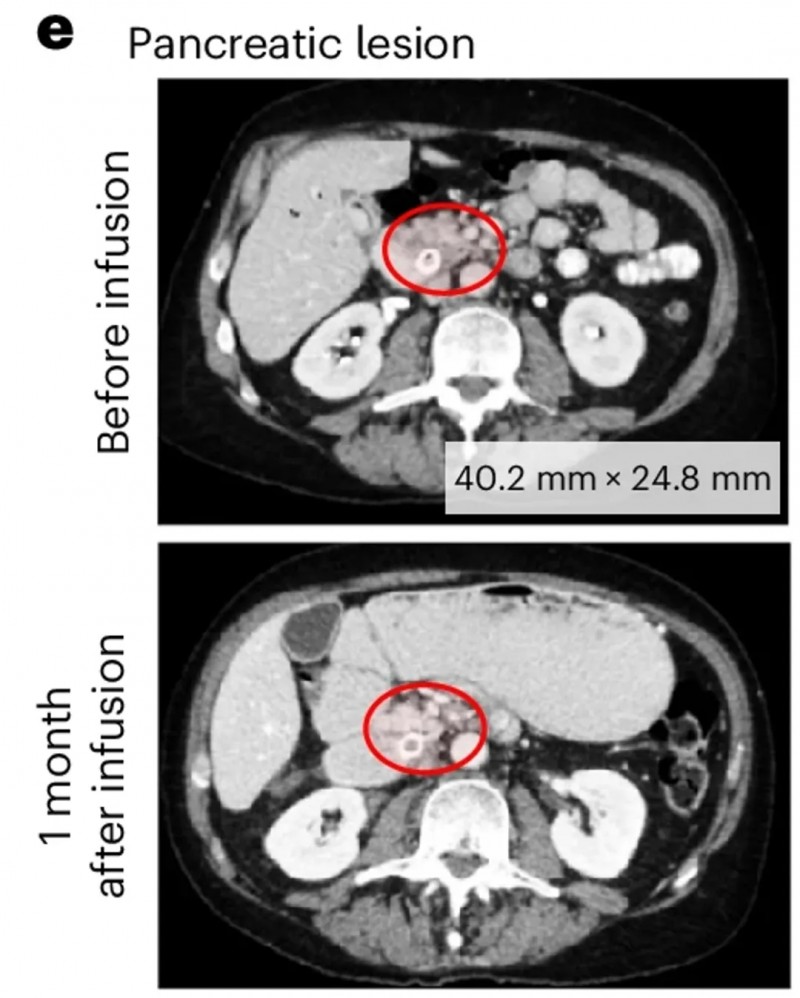

第一例为DL3剂量组患者(UPN394),其肝转移负荷实现放射学改善,但未达到PSA反应;CT扫描清晰呈现了输注前的肝转移灶,以及输注PSCA-CAR-T细胞1个月后的疾病反应(详见下图c)。

▲图源“Nature Medicine”,版权归原作者所有,如无意中侵犯了知识产权,请联系我们删除

另一例为前列腺癌伴胰腺转移患者(UPN388):输注PSCA-CAR-T前后的CT复查显示,输注前病灶大小为40.2×24.8mm,输注后1个月病变完全消退、已无法测量(详见下图e);尽管因存在骨转移,RECIST评估结果为“病情稳定”,但患者软组织转移灶的放射学表现已有所改善(详见下图b)。